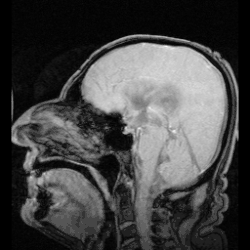

Circulação

O LCR preenche os ventrículos cerebrais, sendo continuamente secretado, de 430 a 500 ml por dia, sendo que renovado em aproximadamente em 6 a 7 horas (3 a 4 vezes por dia) pelos plexos coroides. Desempenha um papel mecânico de sustentação e intervém em certos processos bioquímicos do tecido nervoso.[6]

A maior parte do LCR é produzida nos plexos coroides dos ventrículos laterais. Dos ventrículos laterais, o LCR segue através dos forâmens interventriculares para o terceiro ventrículo e então, via aqueduto cerebral, para o quarto ventrículo. Do quarto ventrículo, o LCR segue pelas aberturas laterais e forâmen medial atingindo espaços subaracnoides e descendo pelo centro da medula espinhal. É continuamente drenado para os seios venosos (através das granulações aracnoides) de volta para a corrente sanguínea.[3] A pressão dessa circulação pode ser alterada por variações na respiração e circulação.

A obstrução de uma das vias de circulação ou excesso de produção do liquor causa um inchaço que evolui para uma hidrocefalia. É necessário intervenção cirúrgica para desobstrução do canal, retirada de tumor e/ou retirada do líquido acumulado.